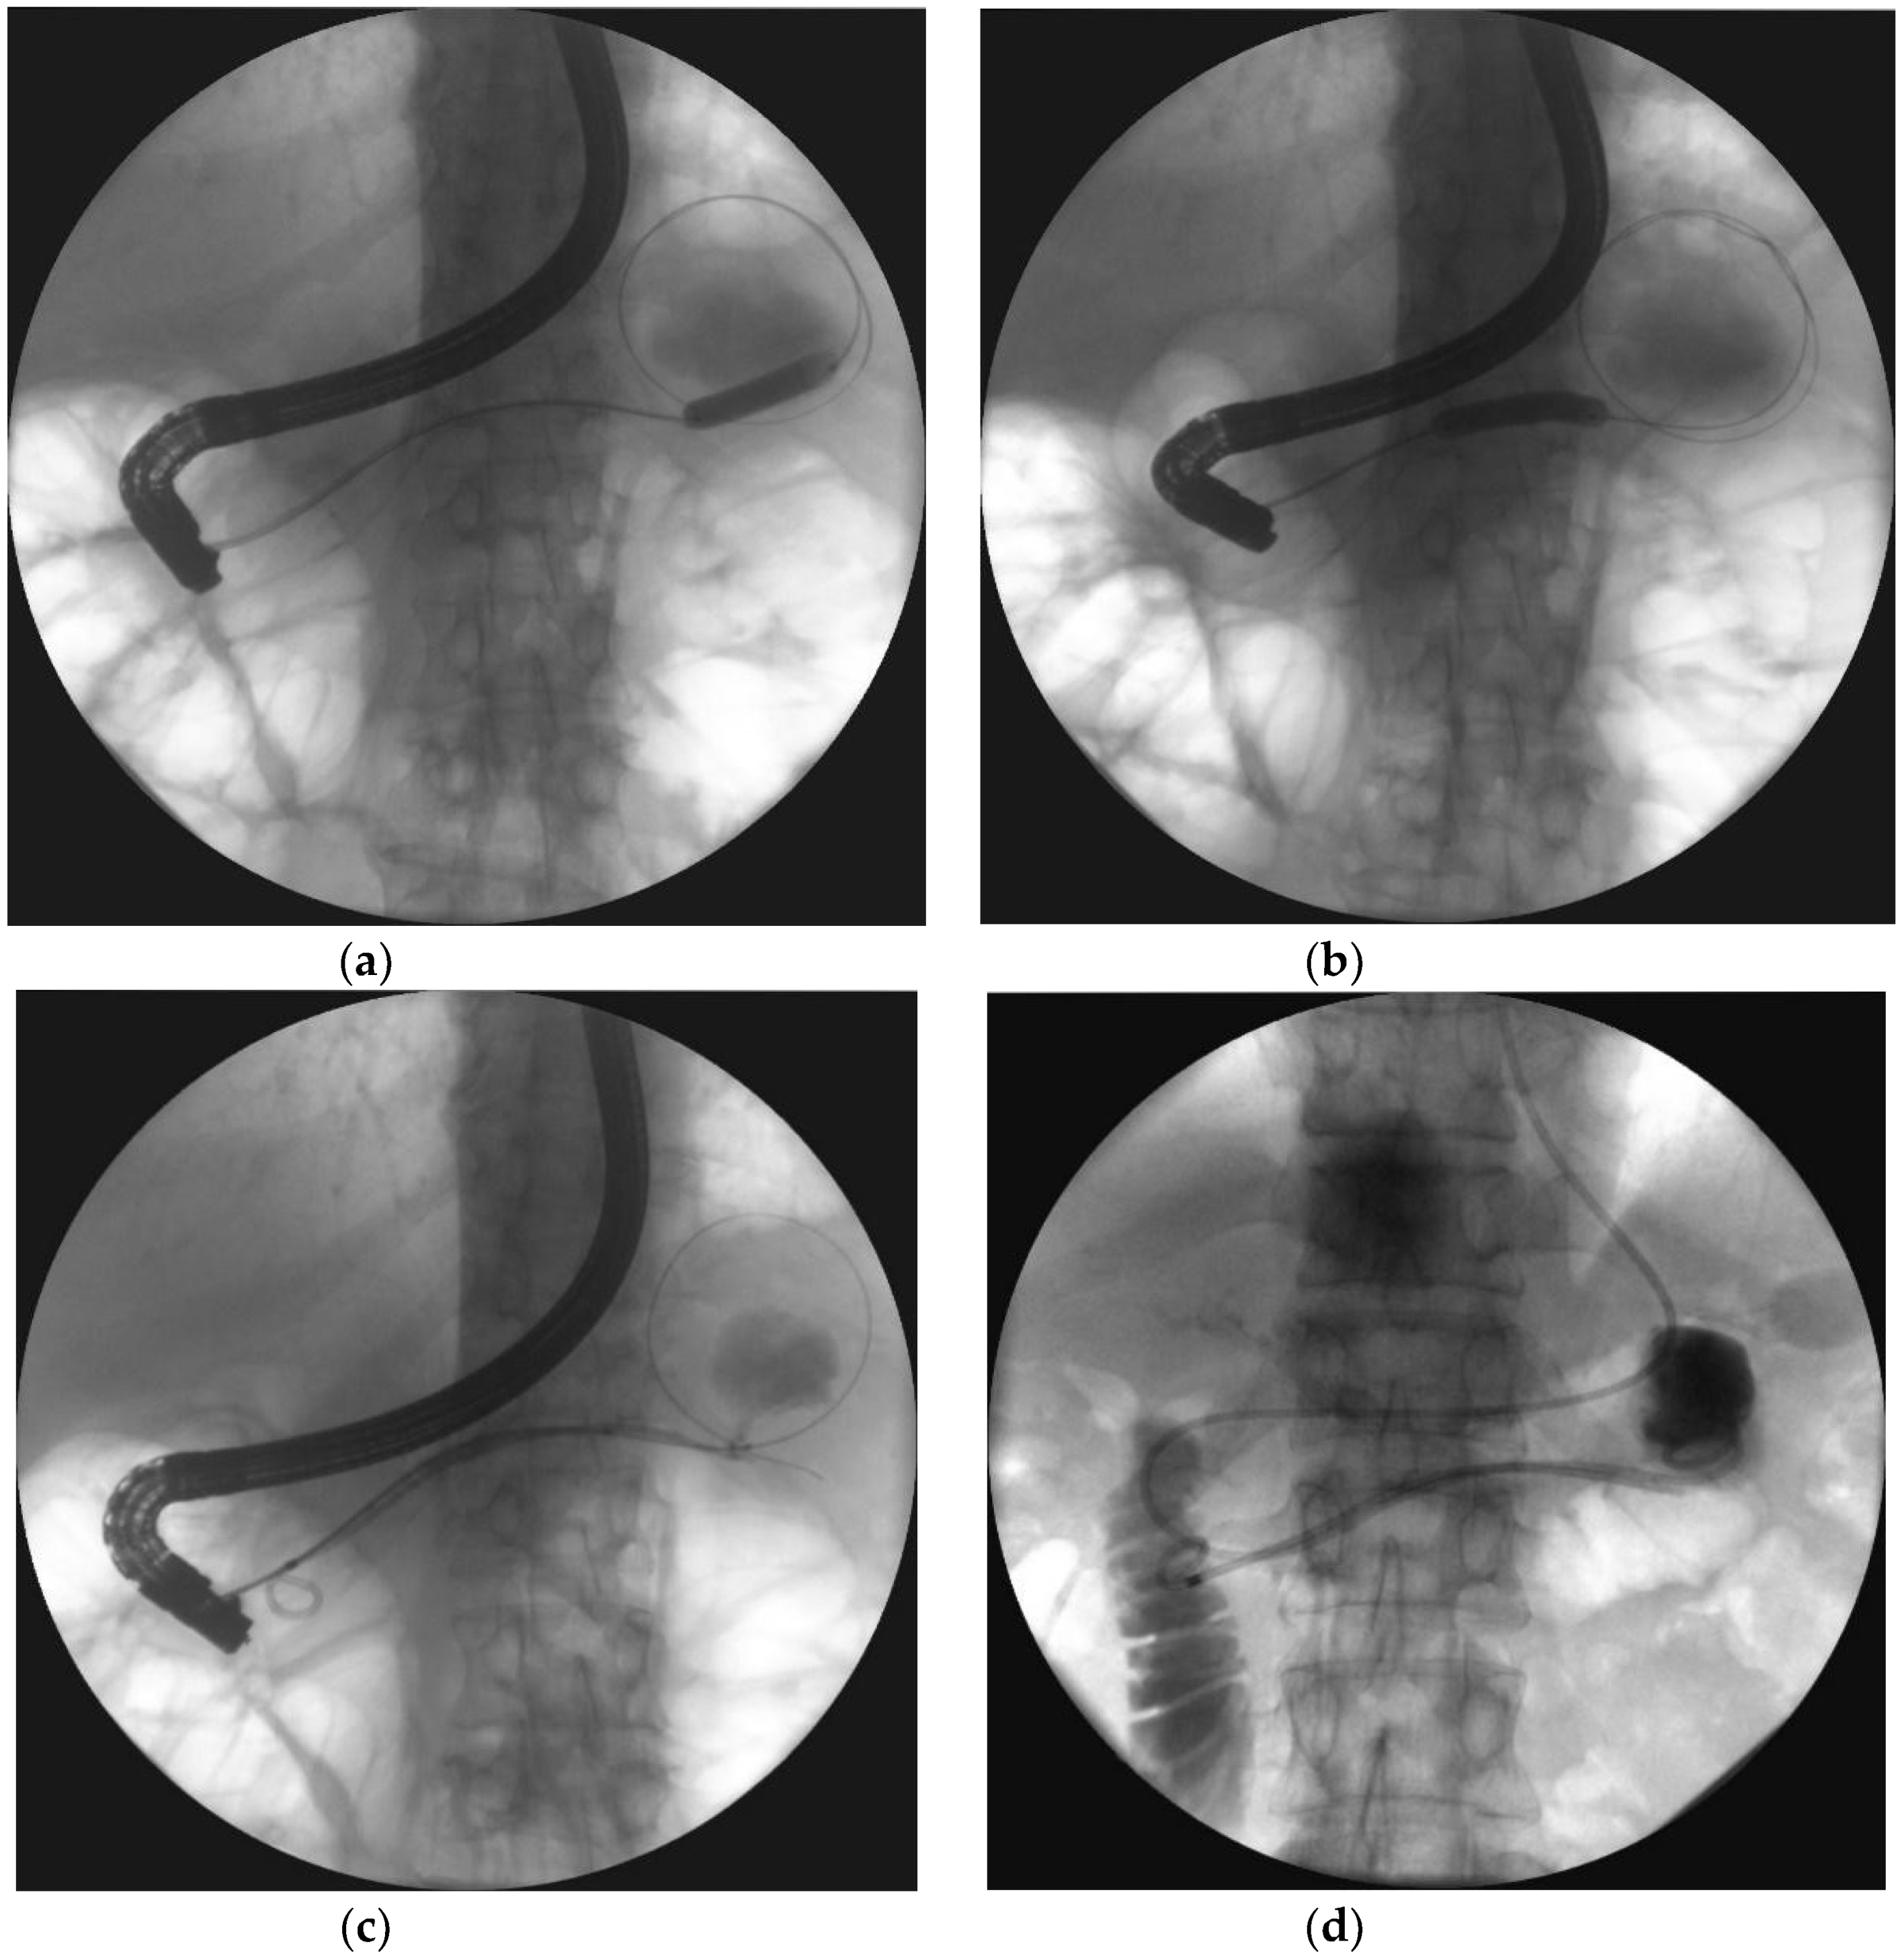

- Jagielski, M.; Smoczyński, M.; Adrych, K. Endoscopic treatment of multilocular walled-off pancreatic necrosis with the multiple transluminal gateway techniques. Wideochir. Inne. Tech. Maloinwazyjne. 2017, 12, 199–205. [Google Scholar] [CrossRef] [PubMed]

- Jagielski, M.; Smoczyński, M.; Adrych, K. Single transluminal gateway transcystic multiple drainage for extensive walled-off pancreatic necrosis—A single center experience. Prz. Gastroenterol. 2018, 13, 242–248. [Google Scholar]

- Jagielski, M.; Smoczyński, M.; Adrych, K. Endoscopic treatment of extensive walled-off pancreatic necrosis with the use of single transluminal gateway transcystic multiple drainage (SGTMD). Pol. Przegl. Chir. 2018, 90, 54–59. [Google Scholar] [CrossRef]

| Multiple transluminal gateway technique (MTGT) | The creation of multiple transmural tracts between the gastrointestinal lumen and the WON cavity. In MTGT another transmural tract between the necrotic cavity and the gastrointestinal lumen was performed in case of multilocular necrotic collections divided by septa. |

| Single transluminal gateway transcystic multiple drainage (SGTMD) | Additional transmural drainage of extensive necrosis through a single fistula. Stents and nasocystic drains were introduced in the subcavities of WOPN through the single transmural tract and canals between necrotic subcavities. |